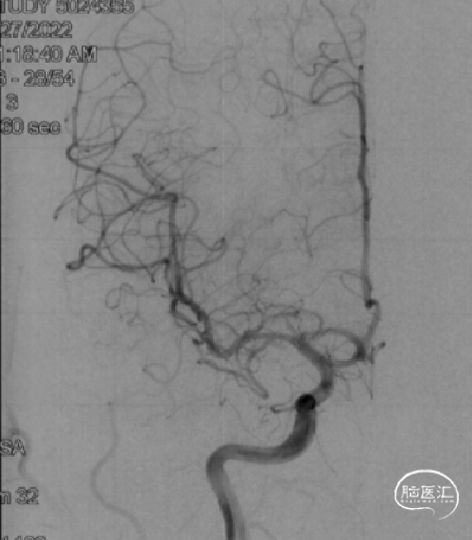

复查脑血管造影示:右侧大脑中动脉支架置入术后,支架位置良好,管腔内血流通畅,未见明显狭窄。

术后2年随访:

复查脑血管造影示:右侧大脑中动脉支架置入术后恢复良好,支架位置精确无误,其管腔血流通畅,未见任何明显狭窄,手术效果满意。

治疗后随访影像对比:

2024-08-07 2Y-FU (正位)

2024-08-07 2Y-FU (侧位)